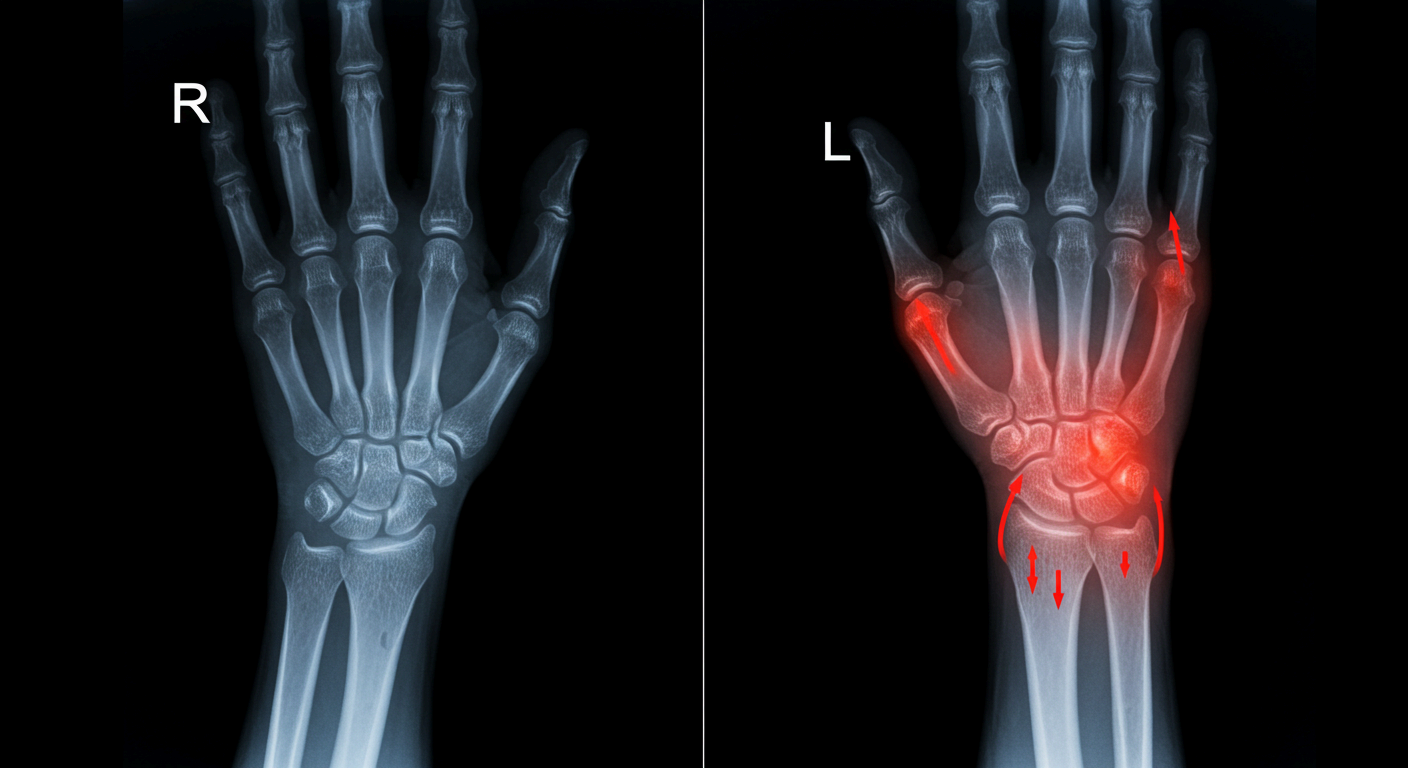

3. 관절염

나이가 들면서 손목 관절의 연골이 닳고 뼈끼리 부딪히면서 퇴행성 관절염이 생길 수 있습니다. 또한 류마티스 관절염처럼 면역 시스템이 손목 관절을 공격하는 질환도 통증의 원인이 될 수 있습니다.

4. 손목 부상과 외상

운동 중 넘어지면서 손을 짚거나, 무거운 물건을 들다 손목이 꺾이는 등의 외상은 골절, 인대 손상, 염좌 등을 유발합니다. 부상 초기에는 단순 타박상처럼 보여도, 시간이 지나면서 통증이 지속되거나 악화될 수 있습니다.